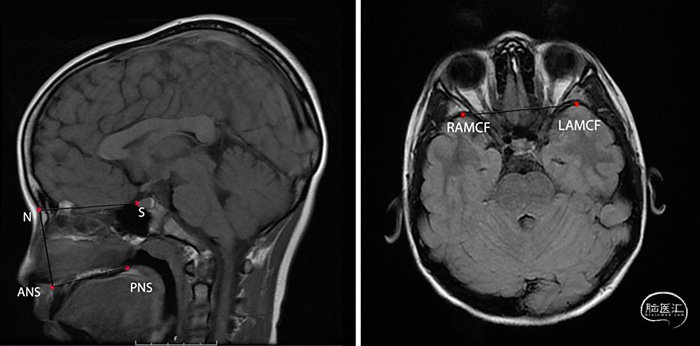

耳鼻喉科和神经外科医生借助于内镜经鼻手术(EES)在良好的可视化条件下进行颅底肿瘤切除,可减少对脑组织的牵拉和损伤。研究表明,与开颅手术相比,EES不增加儿童手术的风险,而且肿瘤切除程度和视力可得到更好的改善。然而,EES是否影响患儿面中部及颅底发育,尚未阐明。美国加利福尼亚州大学圣地亚哥医学院Rady儿童医院的Javan Nation等对此开展研究,采用MRI成像评估EES对儿童面中部及颅底发育的影响,结果发表于2021年5月的《Pediatric Neurosurgery》在线。该研究回顾性分析16岁以下行EES手术的患儿,在术前与术后通过MRI成像评估面中部的解剖结构改变。研究纳入2015年11月至2018年4月间行EES治疗的20例颅底肿瘤患儿,平均年龄10岁;年龄7岁以下者8例(38%);男性11例和女性9例。排除4例使用支架有伪影的患者,1例缺失术后MRI资料,1例患大型错构瘤,侵蚀面中部的解剖结构和1例缺乏面部影像学资料的患儿。将121例正常对照组与20例EES患者按年龄和性别配对。在MRI-T1矢状位和T2轴位各进行3次面中部结构解剖测量(图1)。

图1. 左图MRI-T加权矢状位图像显示测量标志N、ANS、PNS和S。右图MRI轴位图像显示测量的标志RAMCF和LAMCF。N,鼻腔;ANS,前鼻棘;PNS,后鼻棘;S,蝶鞍;RAMCF,右侧颅中窝最前部;LAMCF,左侧颅中窝最前部。比较病例组和对照组患儿的面中部或颅底结构大小测量数据发现,两组测量结果相似,面中部或颅底结构测量值无统计学差异。6例高流量脑脊液漏的患者行鼻中隔皮瓣修补术。T检验和多元回归分析发现,EES对面中部和颅底结构的发育无影响。在评估的变量中,控制年龄和性别后,回归分析发现年龄是面中部或颅底结构大小改变的唯一因素。分析发现病例组患者面中部及颅底结构的发育并未随时间而减慢,事实上,对照组患者在术后19个月和24个月时S-ANS和ANS-PNS的测量值更大。年龄每增加1年,N-ANS、ANS-PNS、N-S和LAMCF-RAMCF分别增加1.3、0.9、0.7和0.6mm。女性N-ANS和LAMCF-RAMCF的平均值分别为1.8mm和2.6mm,小于男性。两组患儿鼻至前鼻棘(N-ANS)、前鼻棘至后鼻棘(ANS-PSN)、鼻-蝶鞍(N-S)和颅中窝中间前部从左到右(LAMCF-RAMCF)的测量值在术后7个月、14个月、19个月和24个月的任何时间点均无统计学差异。该研究结果表明,儿童EES对面中部及颅底发育无明显影响,EES可作为儿童颅底肿瘤切除术的良好选择。